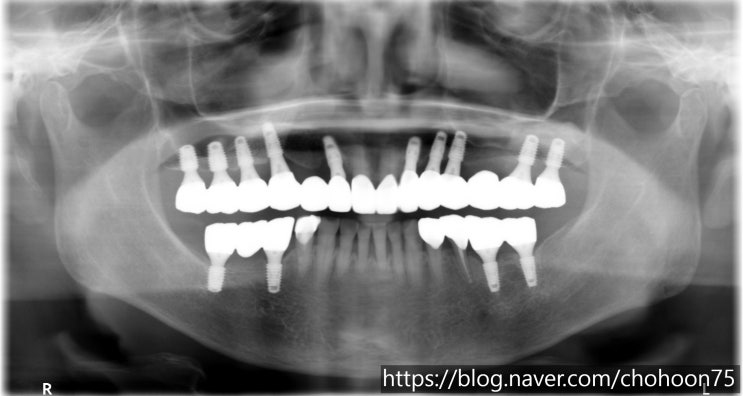

[조훈치과] 오랜 기간 사용 중인 임플란트 케이스(20년 이상)

안녕하세요. 조훈 치과입니다. 임플란트의 수명은 보통 10~15년 정도라고 알려져 있지만 성공적인 임플란트...